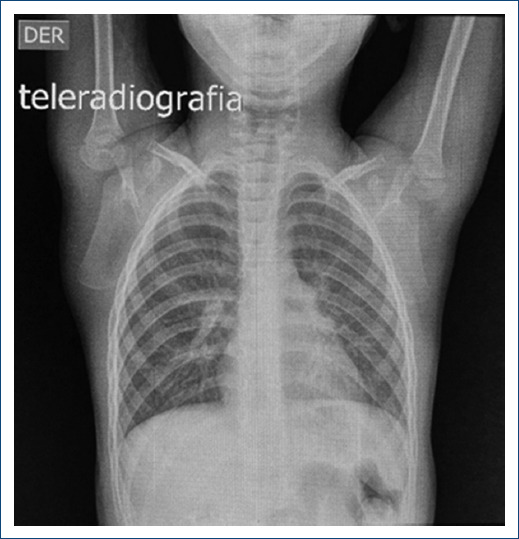

主动脉瓣上狭窄(SVAS)是一种与威廉姆斯-伯伦综合征有关的先天性畸形。其特点是窦管交界处严重狭窄。由于弹性蛋白基因的改变,平滑肌层增厚。治疗方法是外科手术,有几种缓解阻塞的技术,从单补片技术到用三个补片置换全部三个主动脉窦。然而,最佳技术仍不明确。本文旨在对 SVAS 的手术技术进行文献综述,并介绍罗伯托-吉尔伯特-埃利萨尔德医院对一名 4 岁婴儿应用 Doty 技术的情况。

Supravalvular aortic stenosis (SVAS) is a congenital malformation associated with Williams-Beuren syndrome. It is characterized by severe stenosis of the sinotubular junction. The smooth muscle layer is thickened due to an alteration of the Elastin gene. The treatment is surgical and there are several techniques to relieve obstruction which range from the single-patch technique to the replacement of all three aortic sinuses with three patches. However, the optimal technique is still unclear. The objective of this article is to carry out a bibliographic review of surgical techniques for SVAS and the description of the application of the Doty technique for a 4-year-old infant at the Roberto Gilbert Elizalde Hospital.